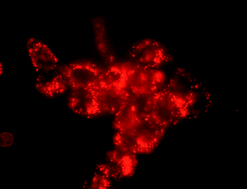

Three novel water soluble, non-ionic, zinc phthalocyanines (Pcs) have been synthesized and their spectroscopic and photodynamic properties investigated in aqueous media. One of the three compounds was shown to be significantly less aggregated, when compared to the other two compounds, and this effect was found to be related to both the nature of the substituent, and also the position at which it is attached to the macrocycle. Photodynamic activity and cellular uptake by human adenocarcinoma cells (HT-29) was shown to be linked to the aggregation state of the Pcs in water.

Graphical abstract: Glycerol and galactose substituted zinc phthalocyanines. Synthesis and photodynamic activity